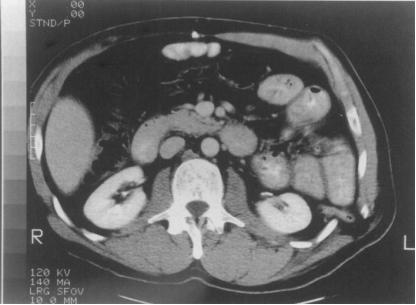

CT、MRI 不仅能明确疝环的大小、周围腹壁肌群薄弱程度及与骨组织的关系,还能提示疝内容物的性质和进一步排除其他性质的病变,可指导临床选择合适的手术方式。

CT 显示左侧腰疝(上述文献截图)